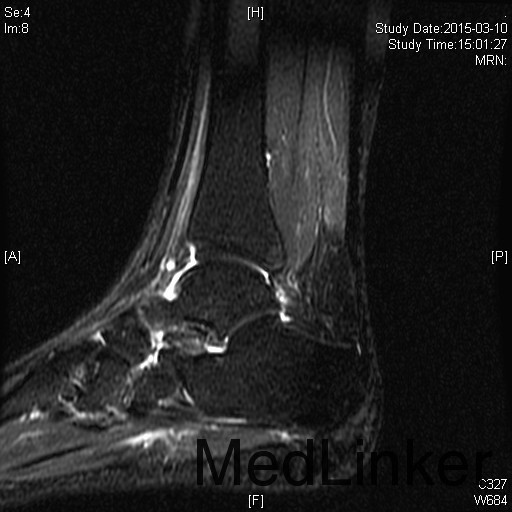

左踝扭伤后肿胀疼痛伴活动受限半年

查体:左腓肠肌萎缩,左踝轻度肿胀。左踝关节ROM较对侧降低,以背伸活动受限最明显。距腓前韧带处未及明显压痛。左踝内、外侧关节间隙压痛(+)。ADT(-),外侧应力试验(-)。左下肢肌张力正常、感觉正常。 辅检:MRI示“左踝关节积液”

诊断:左踝关节创伤性滑膜炎 治疗:左踝关节镜下滑膜清理、胫骨前缘成形

随访:患者术后即刻踝关节活动度恢复正常,2周恢复正常行走。 讨论:踝关节扭伤很常见,扭伤后会发生各种各样的情况。此患者扭伤后继发了滑膜炎,并伤及了关节软骨。这种情况应进行关节镜手术治疗。此外,核磁共振对关节疾患的诊断也是有限的,关节镜才是黄金标准。